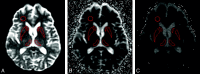

Background and purpose: DWI using a standard b-value of 1000 s/mm(2) has emerged as the most sensitive sequence for the diagnosis of CJD. The purpose of this study was to investigate whether DWI at a high b-value (b = 3000 s/mm(2)) and ADC measurements in the basal nuclei improve the diagnosis of vCJD and sCJD compared with visual assessment of DWI at a standard b-value (b = 1000 s/mm(2)).

Materials and methods: Eight patients with vCJD, 9 patients with sCJD, and 5 healthy volunteers underwent DWI at b = 1000 s/mm(2), and 5 vCJD patients, 4 sCJD patients, and 1 growth hormone-related CJD patient underwent DWI at b = 3000 s/mm(2). Two consultant neuroradiologists performed a visual comparison of the b = 1000 and b = 3000 images. Mean MR SI and ADC values were determined for C, P, and DM thalamus ROIs bilaterally at each b-value. SI ratios for each ROI relative to white matter were calculated.

Results: In 9 out of 10 patients, the higher b-value images were more sensitive to SI change, particularly in cortex and thalamus, with higher SI ratios at b = 3000 in the DM thalamus. For sCJD at b = 1000, we found significantly lower ADC values in the C and P compared with controls (mean C ADC = 587.3 +/- 84.7 mm(2)/s in sCJD patients versus 722.7 +/- 16.6 mm(2)/s in controls; P = .007), and at b = 3000, the differences were more pronounced. In comparison, in vCJD at b = 1000, ADC values were elevated in the Pu (mean Pu ADC = 837.6 +/- 33.0 mm/s(2) in vCJD patients versus 748.0 +/- 17.3 mm/s(2) in controls; P < .001) but failed to reach significance at b = 3000.

Conclusions: Our results demonstrate that b = 3000 DWI, being more sensitive to slowly diffusing tissue water, is more sensitive to pathology in sCJD than is conventional DWI. High-b-value DWI increases confidence in the radiologic diagnosis of human prion disease.